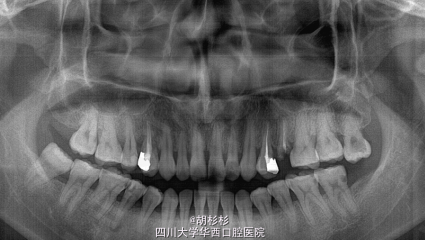

诊断:25牙残根 处理:拔除25牙的同时植入种植体

25牙残根,曾行根管治疗;14牙和24牙均已行根管治疗+冠修复